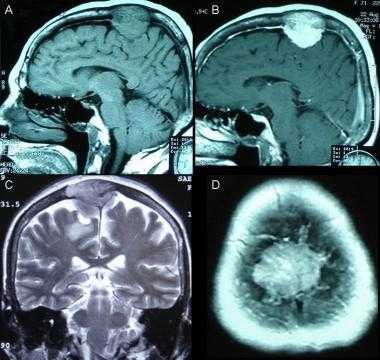

Метастазы головного мозга на МРТ. Фото. Определяются множественные метастазы в мозг при раке легкого: слева в режиме Т1-ВИ в виде гипоинтенсивных образований, справа — в режиме Т2-ВИ виде множественных участков повышенного сигнала, окруженных зоной перифокального отека. У пациента подтверждена первичная опухоль легкого.

Фалькс-менингиома на МРТ.

А: на Т1-взвешенном МР-изображении отмечается солидное образование, характеризующееся изоинтенсивностью по отношению к твердой мозговой оболочке, инвазией в кость и сдавлением теменных зон коры.

В: На Т1-взвешенном МР-изображении с контрастным усилением видна частично контрастируемая опухоль.

С: На корональном Т2-взвешенном изображении видно изоинтенсивное образование, что соответствует плотной ткани. Такая картина характерна для фибробластных менингиом.

D : На Т1-взвешенном МР-изображении с контрастным усилением визуализируется гиперинтенсивное образование внутри мозгового вещества кости.